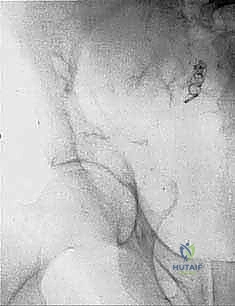

- Plain Radiography (FIG 2): While of limited value for early lesions, it provides an initial overview. As you can see in Figure 2A, we have a large lytic lesion of the right periacetabular region. Figure 2C shows a cartilage-forming lesion in the left ilium. However, plain films often underestimate the true extent of these tumors.

* CT with Intravenous Contrast and 3D Reconstruction (FIG 3): This is our workhorse for assessing bone involvement, destruction, and the critical relationship between the tumor and major pelvic blood vessels. It reveals any distortion of the pelvic anatomy and guides resectability. Figure 3A clearly shows extensive bone destruction and tumor extension into the pelvis and gluteal region. Figure 3C highlights an extensive tumor on the medial aspect of the ilium with destruction of the inner table.